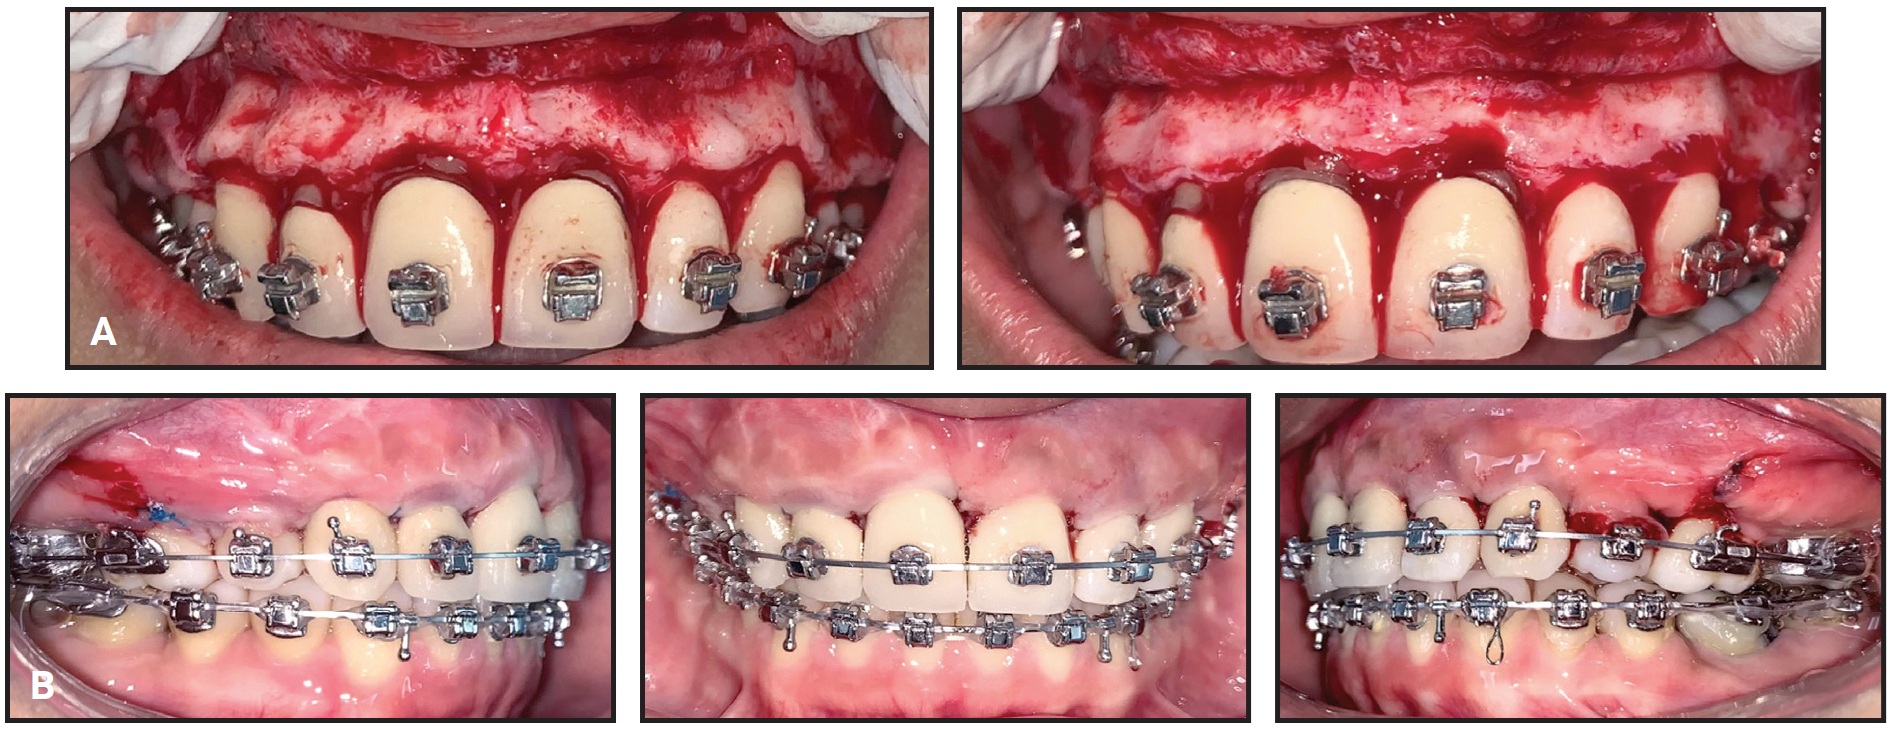

Total treatment time was 22 months (Fig. 11). The patient’s facial profile was more convex and esthetically pleasant. The dental midlines appeared centered in smiling, the black corridors were significantly reduced, and the smile arc was consonant. The incisor display was improved, although a slight asymmetry in gingival exposure could be observed in smiling. Bilateral Class I canine and molar relationships were obtained and the open bite was corrected, with ideal overbite and optimal alignment in both arches. A slightly uneven gingival margin at the upper right canine was attributable both to the initial cant of the maxillary occlusal plane and to a need for further bracket repositioning or wirebending in the finishing phase.

Fig. 11 A. Patient after 22 months of treatment. B. Superimposition of pretreatment (black) and post-treatment (red) cephalometric tracings.

The final panoramic radiograph showed good root parallelism and proper leveling of the interdental bone peaks, with no signs of root resorption. Cephalometric analysis (Table 1) confirmed an improvement in the skeletal sagittal discrepancy (ANB = 1.7°, Wits appraisal = –3.4mm), with an increased SNA angle (78.9°) and normalized lower-incisor inclination (IMPA = 92.5°). The vertical dimension was slightly increased (FMA = 29.8°, MP-SN = 39°), owing to clockwise rotation of the mandible. Regional superimpositions showed extrusion of the upper and lower molars and incisors, but the upper-molar extrusion was more limited than the upper-incisor extrusion, indicating that a clockwise rotation of the maxillary plane had compensated for the clockwise rotation of the mandible.

After debonding, vacuformed maxillary and mandibular retainers were delivered for six months of full-time wear, followed by nighttime-only wear. To further improve vertical stability and tongue function, the patient was referred for speech therapy.